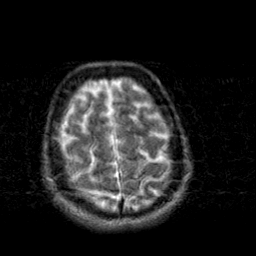

Creutzfeld-Jakob disease: T2-weighted MR -- Slice #19

[Home][Help][Clinical] Slice 19